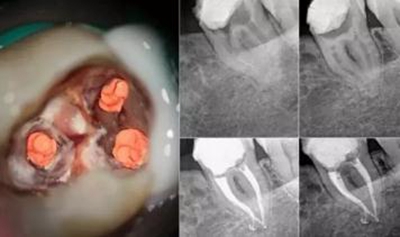

牙醫(yī)在做根管治療時,一般都會抽掉牙神經(jīng),而且又白又肥,想想就覺得特別痛,那牙齒出現(xiàn)什么情況就得抽牙神經(jīng),真的有那么恐怖嗎?究竟有多貴?

比起潔牙、拔牙、補牙這些相對容易理解的概念,根管治療這一專業(yè)名詞還真是有點陌生。所以,為了能夠幫助大家更好的解除疑惑,小編就給大家科普一下根管治療的相關(guān)知識,其中包括“根管治療”和“抽牙神經(jīng)”的不同之處,以及根管治療的具體治療過程。

首先,牙神經(jīng)是在牙髓里邊,抽神經(jīng)只是根管治療其中一步,蛀牙傷及牙髓炎就必須得根管治療,這時牙齒出現(xiàn)敏感,但不會隨便給蛀牙抽神經(jīng),除非牙齒爛掉,只剩下牙根。正常來說,得根據(jù)你的蛀牙程度判定,如果口腔細(xì)菌破壞牙本質(zhì),通常復(fù)合樹脂補牙就好了。當(dāng)你去看牙醫(yī)時,如果醫(yī)生說到牙齒的根管治療,那就需要抽牙神經(jīng)了。

另外針對于磨牙來講,通常磨牙會有3到4個牙根,但是牙根里面的神經(jīng)可能會有多根,正常的磨牙根管治療是指治療3根神經(jīng)的費用,如果這個牙齒的神經(jīng)數(shù)量超過3根那么每多出來一根就要加收一根神經(jīng)的費用。

出現(xiàn)這種情況,可能是醫(yī)生沒有將牙髓清理干凈,導(dǎo)致發(fā)炎感染,這時候就得將填充材料取出,重新再做一次根管治療。記得最后要套上一顆烤瓷牙冠保護原牙,因為牙齒失去牙髓唯一的營養(yǎng)來源,變得又黑又脆弱,跟死牙沒什么區(qū)別,吃東西容易崩壞。所以找個靠譜的牙醫(yī)很重要哦,為了避免二次根管,一定要擦亮眼睛,選一位好牙醫(yī)呢!